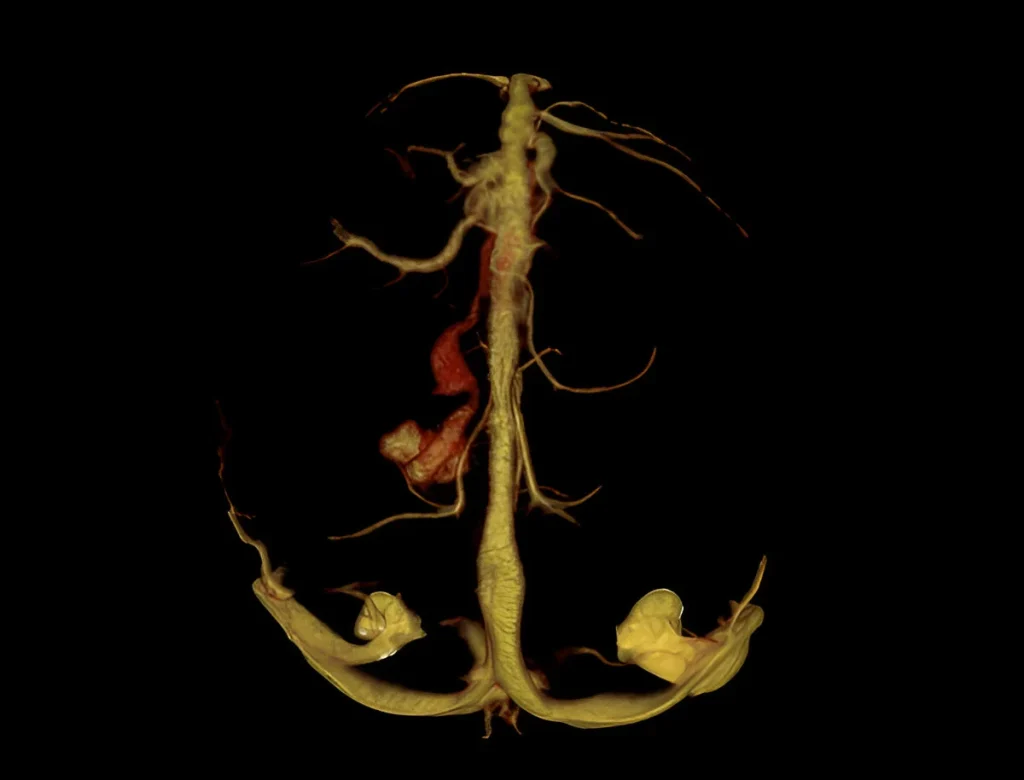

CT Angiography in Navi Mumbai | Henotic Diagnostics

Looking for CT Angiography in Kharghar? At Henotic Diagnostics, we provide advanced, non-invasive CT angiography for precise vascular imaging of the brain, neck, chest, abdomen, pelvis, and limbs. Moreover, this scan detects blockages, aneurysms, malformations, and blood flow issues using multi-slice CT with contrast. In addition, our expert radiologists deliver accurate reports for cardiology, neurology, and vascular care. Therefore, patients in Kharghar, Panvel, Belapur, Nerul, Vashi, and Navi Mumbai can trust us. Book your CT Angiography today!